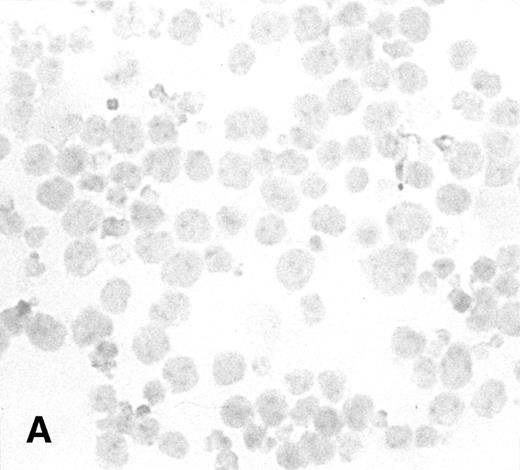

To determine the ability of an MuLV-based retroviral vector to stably infect NK cells, expression of IL-2 and Neo markers was evaluated. The efficiency of a flow-through method was determined by immunostaining for expression of the transgene. As a control, MFG-IRAP–infected NK-92 cells were used. Figure 1 shows staining for IL-2 of cultured P-NK-92 cells, which were negative for intracytoplasmic IL-2, and of transiently transduced NK-92 cells, which contained 10% to 20% stained cells. The percentage range of positive cells was determined by counting a total of 200 cells on each immunostained cytosmear prepared from three different cultures of transiently transduced NK-92 cells. These cultures were not tested by ELISA for the level of IL-2 in the supernatants because of the presence of exogenous IL-2. Instead, a culture of NK-92 cells transduced with the IRAP gene and containing 2% to 3% IRAP-positive cells by immunostaining (not shown) was tested in ELISA for the level of IRAP in the supernatant. At 72 hours posttransduction, the supernatant contained 8.4 ng IRAP/106 cells/48 h. P-NK-92 cells did not produce IRAP.

Immunostaining for IL-2 in transduced but nonselected NK-92 cells. (A) P-NK-92 cells incubated for 48 hours in the absence of exogenous IL-2 prior to staining. (B) Transduced nonselected (48 hours posttransduction) IL-2/Neo/NK-92 cells incubated for 48 hours in the absence of exogenous IL-2 prior to staining. Insert shows an IL-2–expressing NK cell (original magnification ×1,000). The staining reaction was developed with AEC, and the cells were counterstained with hematoxylin. For A and B, original magnification is ×500.

Immunostaining for IL-2 in transduced but nonselected NK-92 cells. (A) P-NK-92 cells incubated for 48 hours in the absence of exogenous IL-2 prior to staining. (B) Transduced nonselected (48 hours posttransduction) IL-2/Neo/NK-92 cells incubated for 48 hours in the absence of exogenous IL-2 prior to staining. Insert shows an IL-2–expressing NK cell (original magnification ×1,000). The staining reaction was developed with AEC, and the cells were counterstained with hematoxylin. For A and B, original magnification is ×500.